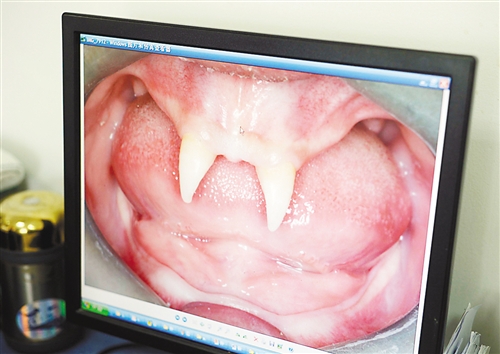

12月18日,16歲的張成(化名)從小到大,只有上顎部分有兩顆牙,看上去更像長(zhǎng)著一對(duì)獠牙。 記者熊明攝

重慶日?qǐng)?bào)訊 每個(gè)人都有牙齒,但對(duì)16歲的張成(化名)來(lái)說(shuō),從小到大,他只有上顎部分有兩顆牙,看上去更像長(zhǎng)著一對(duì)獠牙,這讓他很自卑又易怒。12月18日,在母親的陪同下,他來(lái)到三軍醫(yī)大西南醫(yī)院求助。經(jīng)醫(yī)生檢查,發(fā)現(xiàn)張成患有一種罕見的基因病。

張成是貴州銅仁地區(qū)思南縣人,從生下來(lái)就似乎得了一種怪病,身上毛發(fā)稀少,面部發(fā)育也不好。更奇怪的是,別人家的孩子都長(zhǎng)牙吃東西了,他卻一直長(zhǎng)不出牙齒,最后只在上顎部分冒出兩顆比較突出且對(duì)稱的牙齒,看起來(lái)就像一對(duì)獠牙。